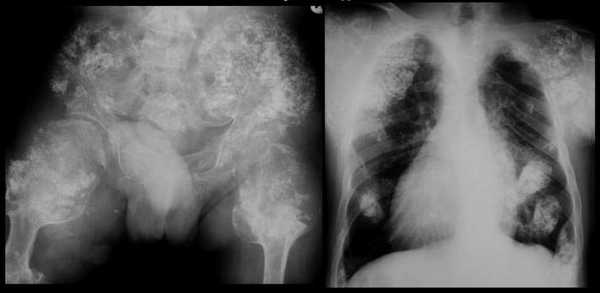

Чтобы выявить какие-либо внутренние нарушения при синдроме Маффуччи рекомендуется провести рентгенологическое исследование, желательного всего тела. Большое внимание в данной ситуации уделяется тем участкам, где наблюдается выпячивание тканей, изменения и укорочение конечностей. Рентгенологическая симптоматика состоит из признаков хондродисплазии разной степени тяжести.

На снимках специалист может отметить ассиметричное поражение, которое характеризуется утолщением укороченных и деформированных костей трубчатого типа. При этом заметны эксцентричные просветления. Такое нарушение очень часто диагностируется в тазовой области, на лопатках, ребрах. По мере роста ребенка наблюдаются в трубчатых костях, где есть утолщения и искривления, просветления округлой формы, могут присутствовать энхондромы.

Маффуччи синдром (Maffucci)